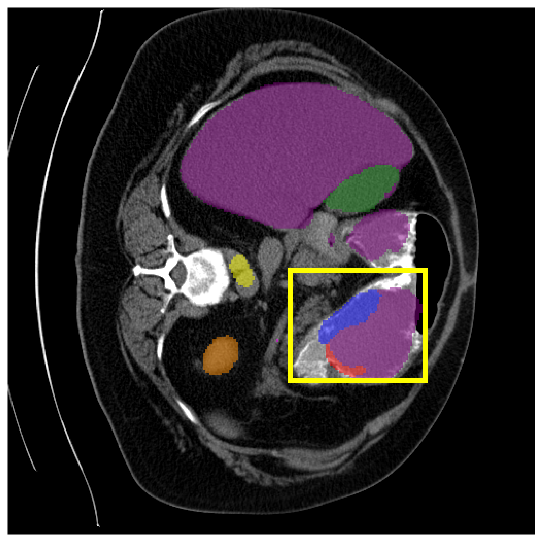

4.3.2 Visual Comparisons

Visualization of our method on the Synapse and ACDC datasets is shown in Fig. 3(a) and Fig. 3(b). For the Synapse dataset illustrated in Fig. 3(a), FCT failed to accurately segment SM and GB, while MERIT achieved precise segmentation of SM but struggled with GB. In contrast, our method achieved accurate segmentation of both SM and GB. Regarding the ACDC dataset shown in Fig. 3(b), while previous methods achieve comparable segmentation of the Myo and LV to the GT, they exhibit noticeable errors on the RV, including invasion into adjacent organs and misrecognition. On the other hand, our method accurately segments across all three structures Myo, LV, and RV, performing as precisely as the GT. We demonstrate the superiority of our method quantitatively and qualitatively.